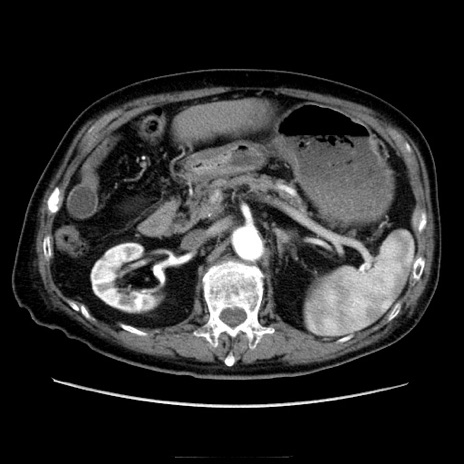

症例21(横断像)

【症例】70歳代男性

【主訴】腹痛

【現病歴】肝硬変・肝細胞癌にてかかりつけの方。約9時間前に食後より腹痛出現。症状が徐々に増悪し、嘔吐出現したため来院。

【既往歴】肝硬変、肝細胞癌(RFA、TACE後)

【身体所見】意識清明、表情苦悶様、BT 36℃、BP 129/78mmHg、P 88bpm、SpO2 97%(RA)、右上腹部から心窩部にかけて圧痛あり、反跳痛なし、筋性防御あり。

【データ】WBC 5800、CRP 0.16